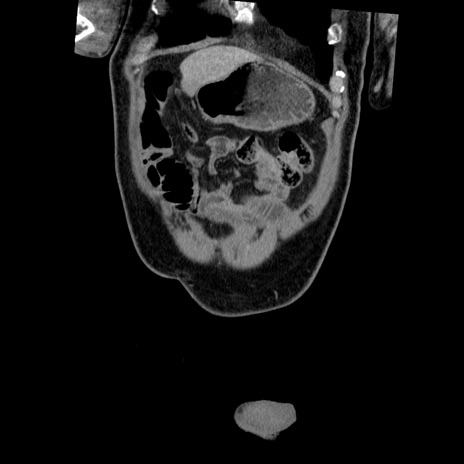

横断像

【症例】50歳代男性

【主訴】腹痛

【現病歴】AVMからの被殻出血のため回復期リハ病棟入院中。 本日午後3時頃急に下腹部痛が出現した。

【既往歴】AVM、被殻出血、虫垂炎、高血圧

【身体所見】意識晴明、左半身不全麻痺、会話の理解は良好、36.5°C、腹部:膨隆、全体に板状硬、下腹部正中に圧痛点あり、反跳痛-、筋性防御不明、右下腹部にope scar

【データ】WBC 9400、CRP 0.06